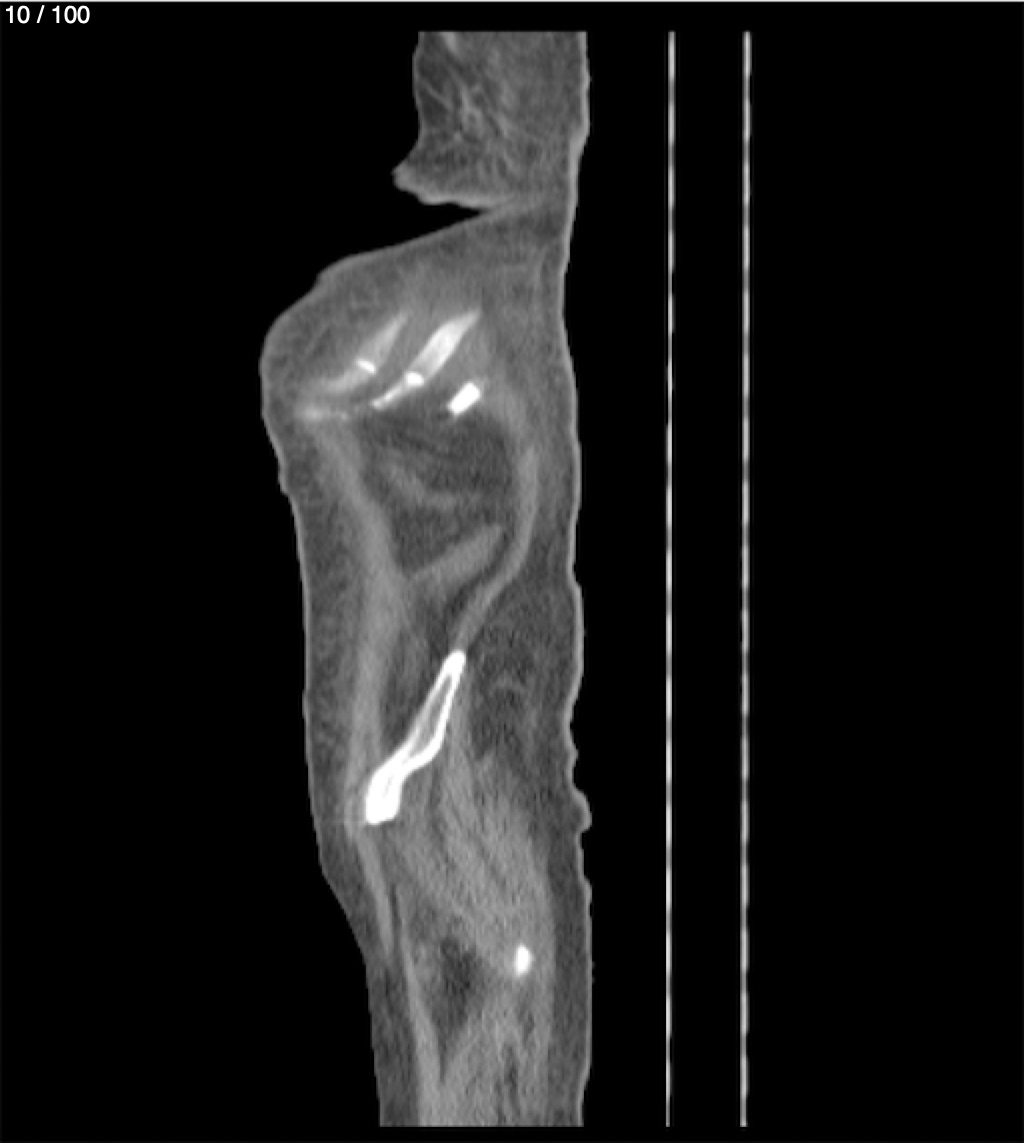

Hilda Geronimo Mendez 60A - T.C Abdomen Simple